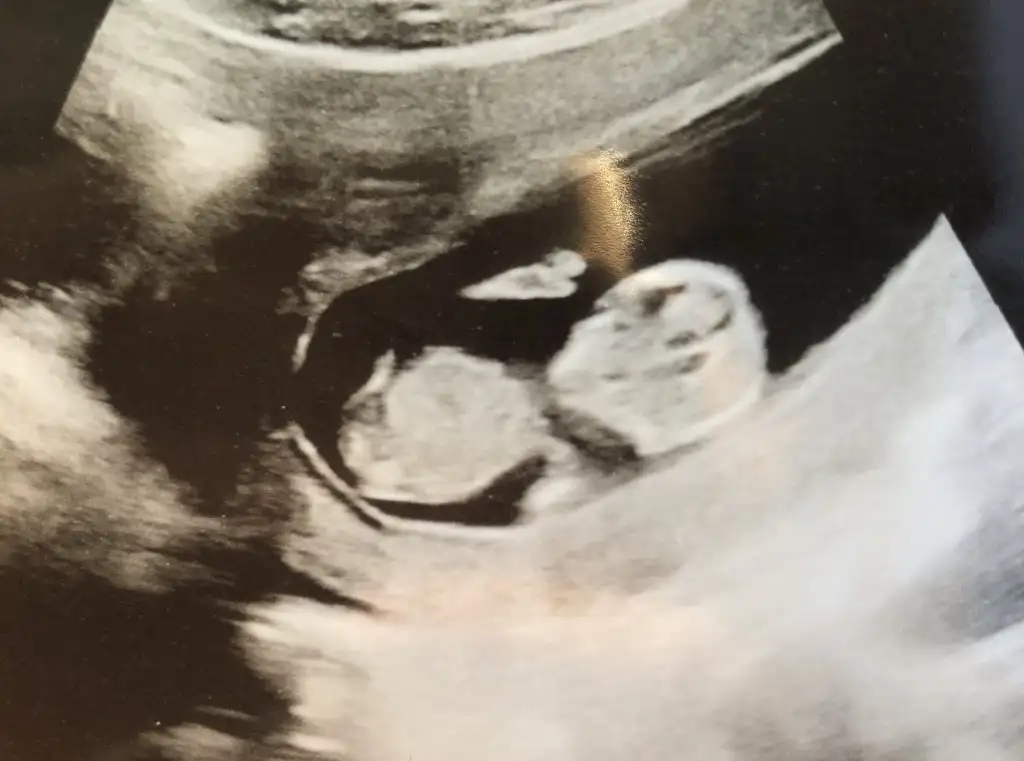

dr soylemeden siz gorun genital nub teorisi ( bebegin cinsiyeti)

Kızlar yorum istiyorum doktor daha küçük dedi 12 haftada ☺️☺️